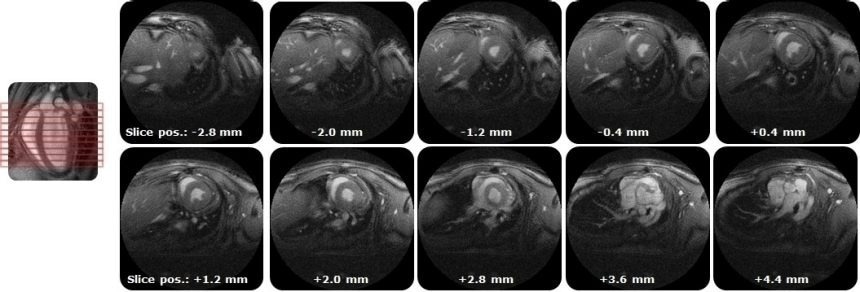

IntraGateUTE, with its radial readout, enables high-quality cardiac cine data in shortest measurement time. Image Credit: Bruker BioSpin Group